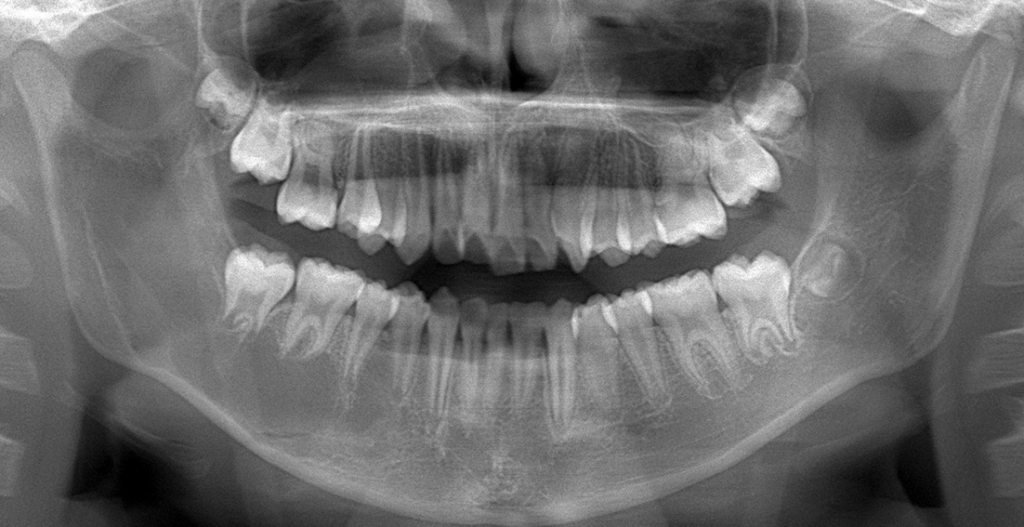

画像所見:右側下顎小臼歯部骨体から下顎枝に至る単房性X線透過像が認められた。境界は歯槽部の一部では比較的明瞭であったが、その他の部位ではあきらかな辺縁硬化像は認められずやや不明瞭であった。歯槽部では槽間中隔に入り込む所見を示し、隣接する歯の歯根吸収、傾斜は認められなかった(図2)。

今回は2025年12月号より、「下顎臼歯〜下顎枝部のX線透過像」についてです。